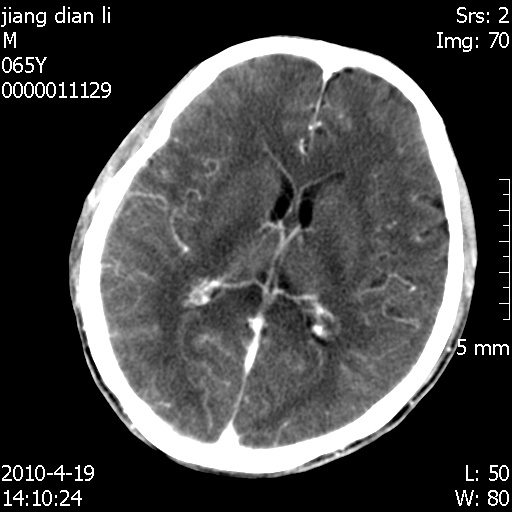

老年男性,突发左下肢无力1天,其余有价值的检查都没有。平扫ct值大约60hu,增强后ct值没什么改变,请大家讨论一下这个病例是什么?说明诊断理由。

今天上班后发现病人前天复查(4月18日发病,19日初诊,22日复查),三个病灶均明显增大,边缘仍旧清楚,水肿加重,右侧脑室基本闭塞。

今天遇到临床医生,询问病人情况,病人已经死亡。

最后看到的病人右侧瞳孔呈针尖大小,估计是继发脑干梗死,而非脑疝死亡。

遗憾! 复习了复查片:发现顶叶出血灶破入侧脑室,侧脑室体部见少许高密度。